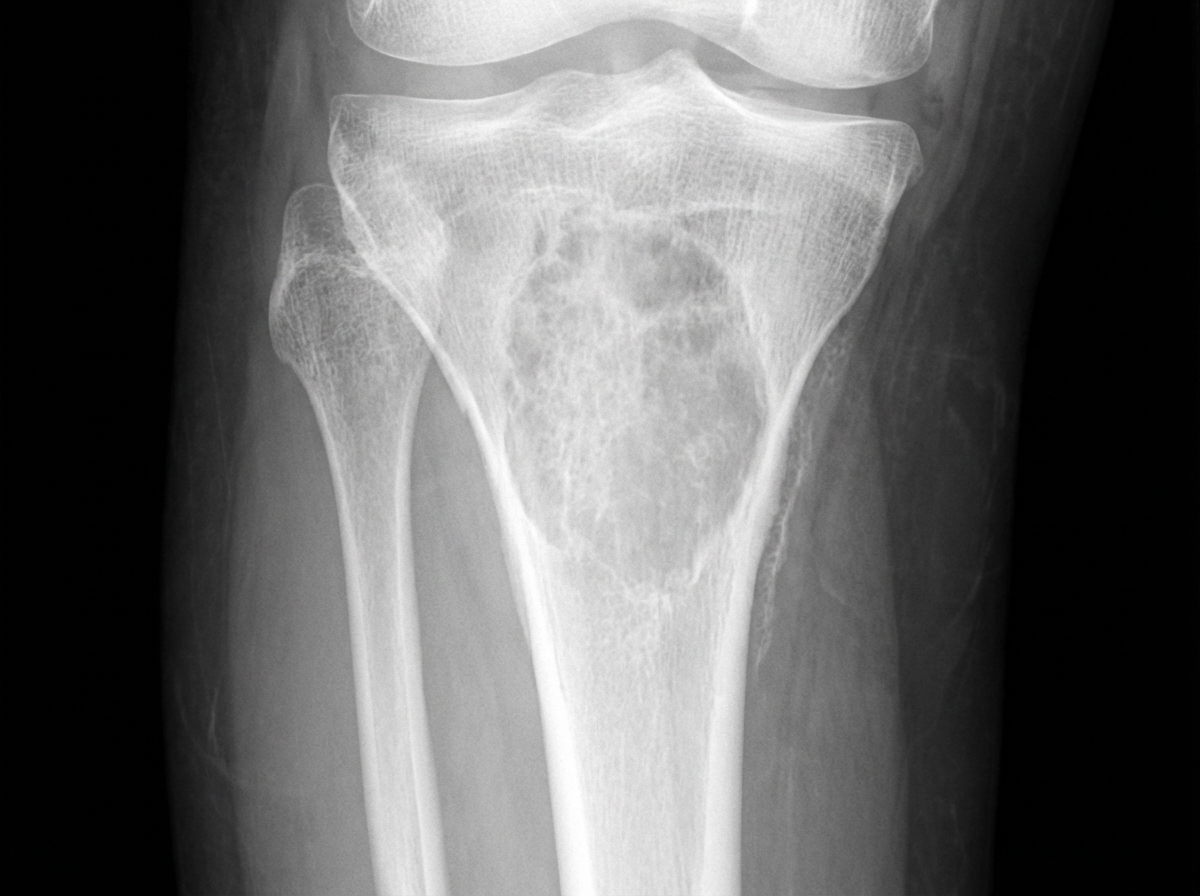

A 40-year-old female presented with severe pain in the left forearm and left ankle following trauma. She reported difficulty walking and swelling in her right upper leg. She also experienced ankle pain and painful ankle joint movements for approximately two years. Relevant abnormal biochemical parameters included: raised serum calcium (11.9 mg/dl), raised alkaline phosphatase (717 U/L), low inorganic phosphorus (1.3 mg/dl), and raised serum parathyroid hormone (1265 pg/l). Protein electrophoresis for M band was negative. An X-ray of the right leg is provided. What is the most likely diagnosis given the clinical presentation and biochemical findings?

Explanation: ***Hyperparathyroidism*** • Classic biochemical triad of **hypercalcemia (11.9 mg/dl)**, **hypophosphatemia (1.3 mg/dl)**, and **elevated PTH (1265 pg/l)** confirms primary hyperparathyroidism. • **Elevated alkaline phosphatase (717 U/L)** indicates increased bone turnover, while fractures and bone pain suggest **osteitis fibrosa cystica** with possible **brown tumors**. *Multiple Myeloma* • Would typically show **positive M band** on protein electrophoresis and **lytic bone lesions** without sclerotic borders. • Usually presents with **normocalcemia** or **suppressed PTH** due to **PTH-related protein (PTHrP)** secretion, not elevated PTH. *Paget's Disease of Bone* • Characterized by **mixed lytic and sclerotic lesions** with **cortical thickening** and **bone deformity**. • Typically shows **normal calcium**, **normal or slightly elevated phosphorus**, and **normal PTH** with isolated **alkaline phosphatase elevation**. *Osteomalacia* • Usually presents with **low or normal calcium**, **low phosphorus**, and **elevated or normal PTH** as secondary response. • **Alkaline phosphatase** is typically **mildly elevated**, not markedly raised as seen in this case with bone resorption.